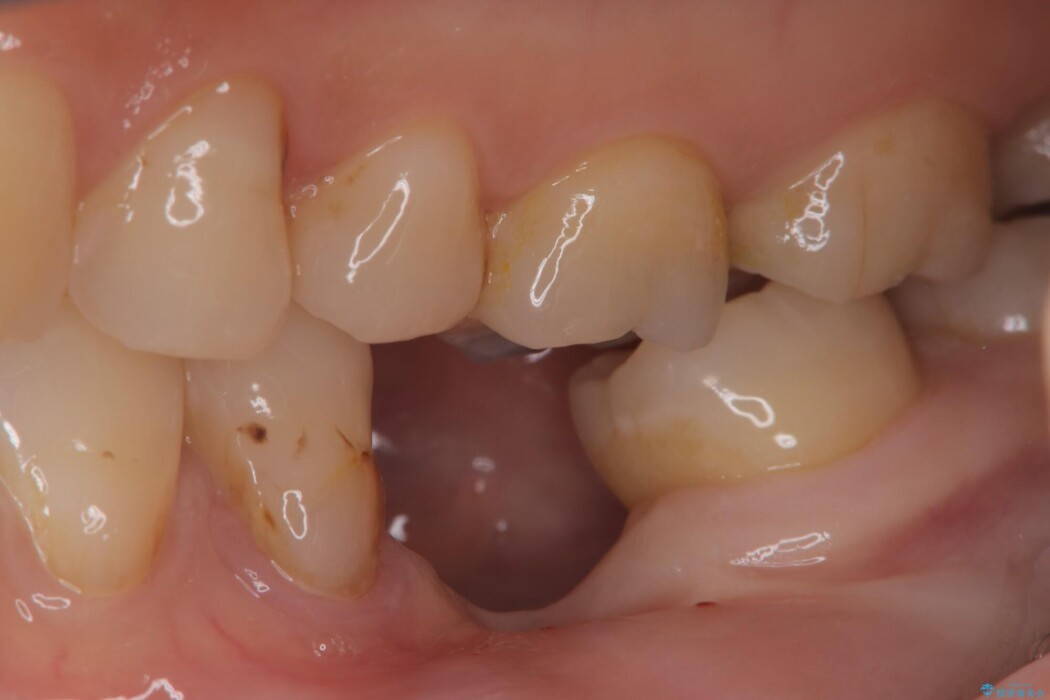

左下奥歯の抜歯後、長期間放置していたために、周囲の骨が吸収してしまいました。 特に垂直的な高さが不足しており、通常の術式ではインプラント埋入が難しい状態でした。

一般的に、骨が少ない場所への埋入は高度な技術を要しますが、今回は適切なサイズ(8.5mm)を選択し、埋入する深さを緻密にコントロールすることで、周囲の神経や重要な組織を傷つけることなく安全に処置を完了しました。

現在はインプラントが骨としっかり結合し、被せ物を装着して力強く噛めるようになっています。長期間の放置によって低下していた咀嚼機能が回復し、「もっと早く相談すればよかった」と喜んでいただけました。